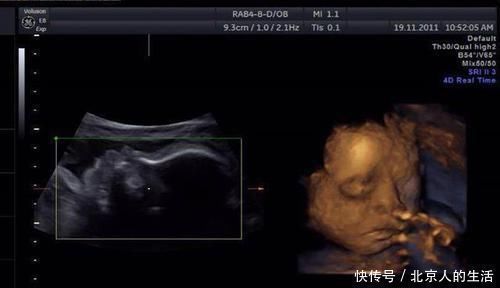

检测畸形儿的最重要方式是四维彩超,但千万不要把这项检查太过“神化”,它也不是万能的。

四维彩超主要显示胎儿在子宫内的实时动态影像,方便医生进行全方位观察,若发现异常也能及时进行处理。